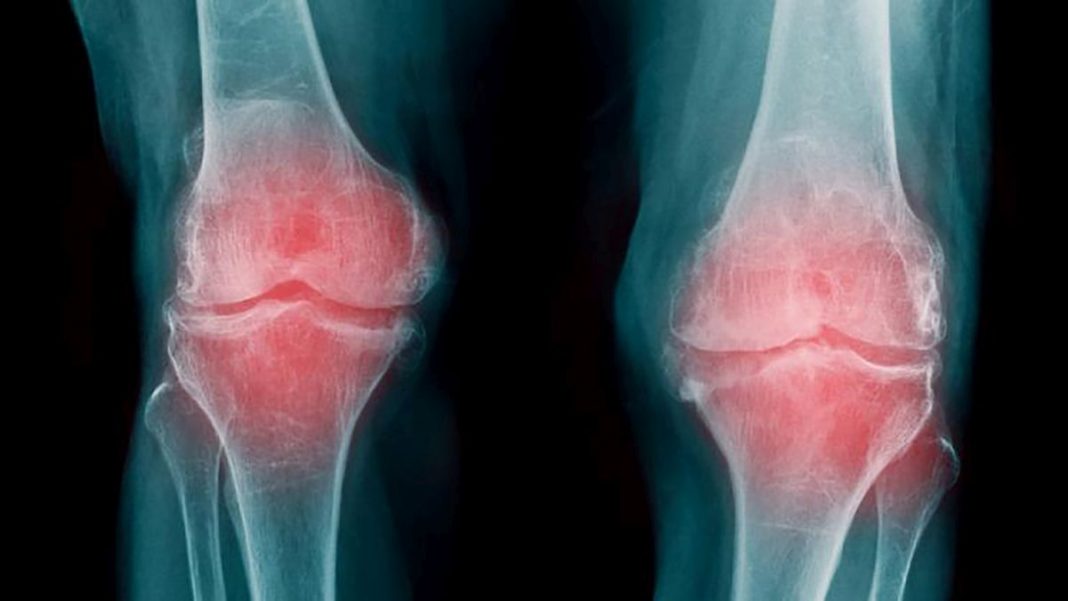

La artrosis es una enfermedad degenerativa que ocasiona el deterioro y la destrucción del cartílago encargado de recubrir las articulaciones de nuestro cuerpo. Se da de forma más común entre las mujeres en el rango de edad que va de los 25 a los 50 años.

Entre sus síntomas, encontramos el dolor y la hinchazón de las articulaciones. Cuanto más te muevas, si padeces la dolencia, más molestia notarás. Es lo que se conoce como dolor mecánico y se alivia cuando reposamos. No es plenamente hereditaria, pero, en caso de que alguien en tu familia sanguínea sufra artrosis, es más fácil que tú la acabes padeciendo. A la causa anterior, se le añaden otras, que tienen que ver con el estilo de vida que lleves. No tiene cura. Sin embargo, el control de tu peso, el ejercicio físico o tu dieta la pueden aliviar. En cambio, las malas posturas, el sedentarismo y el sobrepeso favorecen su aparición y agravamiento.